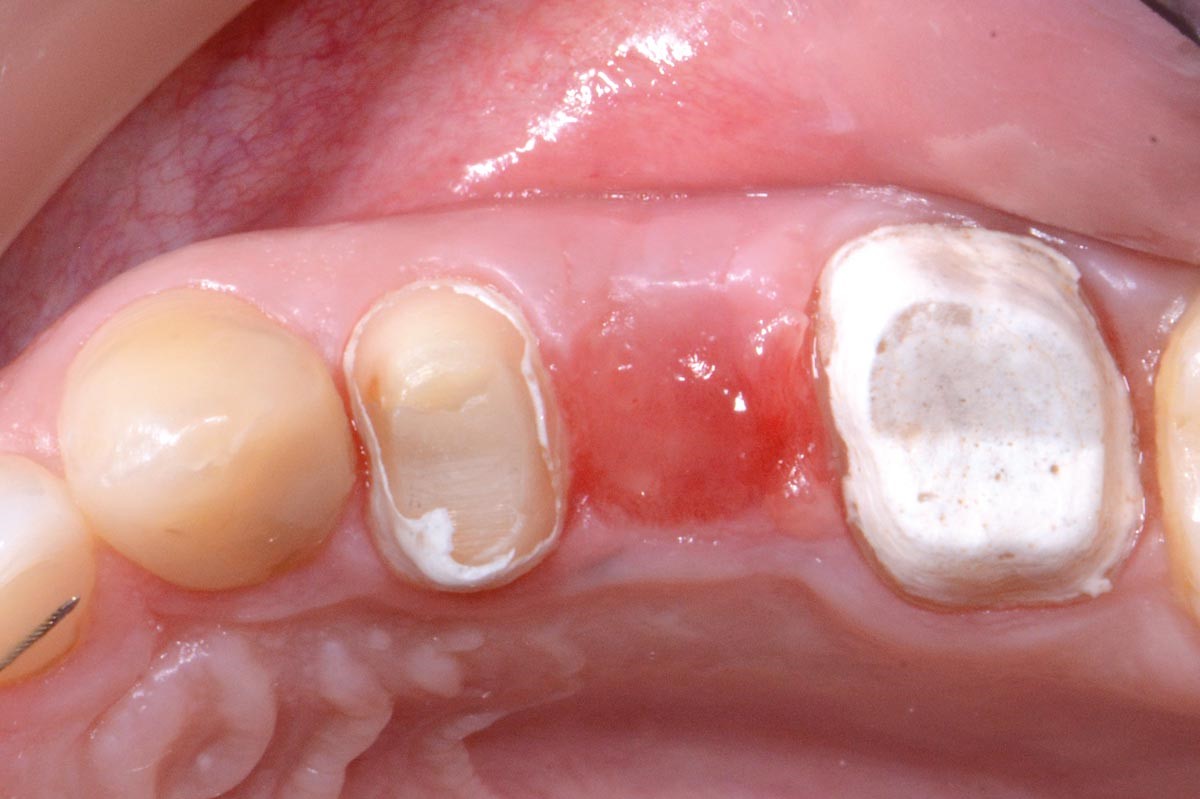

01/16 - Initial clinical situation: 9 mm pocket depth associated with root fractureFull bone regeneration in extraction socket augmented with maxgraft® and Jason® membrane – Dr. C. Landsberg